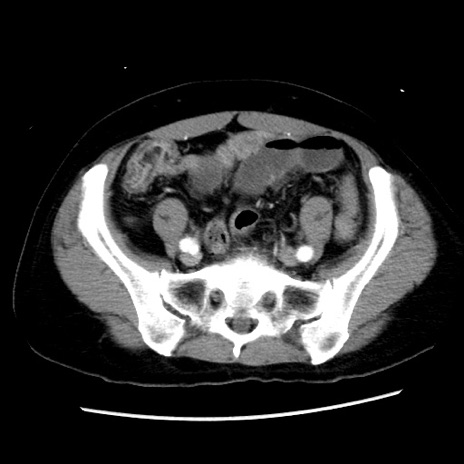

症例10(横断像)

【症例】 50歳代女性

【主訴】 腹痛

【現病歴】前日生レバーを食べた。今朝に排便あり。 昼前に突然発症の腹痛を生じ、当院救急外来を受診した。

【既往歴】 子宮筋腫にてで子宮全摘後

【身体所見】 意識清明、腹部:平坦、軟、下腹部やや左を中心に圧痛・反跳痛あり、筋性防御あり

【データ】WBC 7800、CRP 0.07